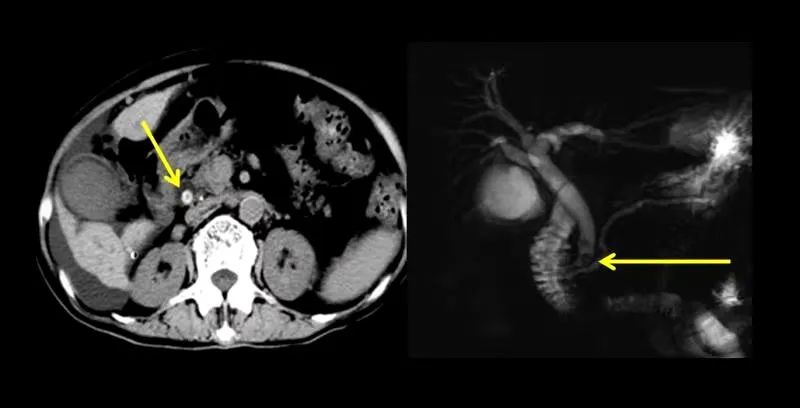

胆总管下端结石CT和MRCP图